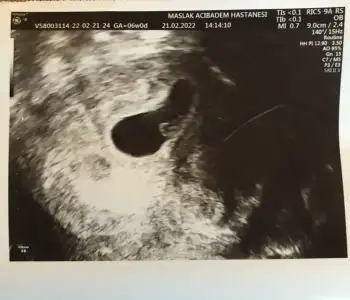

Kızlarrrr bu da benim minnoşum ❤️

Bu arada transfer tarihine göre 6+0 mışım nedense yanlış hesaplamışım 😀